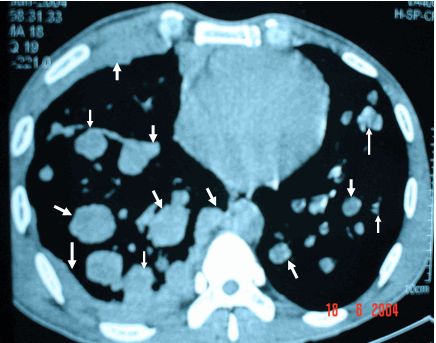

Ung thư phổi màng phổi thứ phát trên XQ

Tế bào ung thư gốc được gọi là ung thư nguyên phát, và khi nó lây lan thì được gọi là ung thư thứ phát hay di căn. Bất cứ loại ung thư nào cũng có thể lây lan sang phổi. Mời các bạn cùng tìm hiểu thêm những thông tin ngay dưới đây để hiểu rõ hơn nhé!